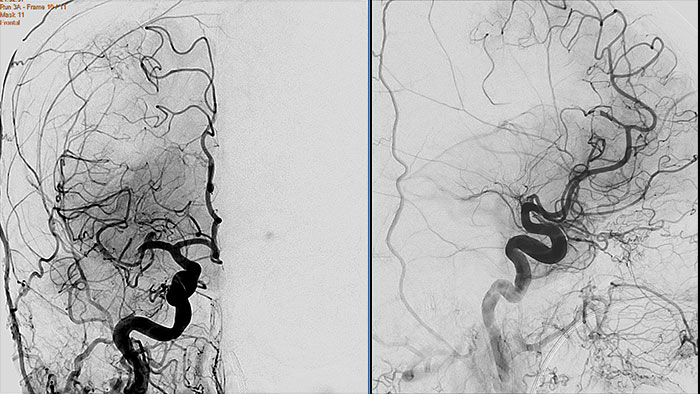

XA Vascular Processing - DSA (in MMV)

Contrast arterial structures with surrounding bone and soft tissue to assist in identification of vascular abnormalities

The XA Vascular Processing – DSA (in MMV) expands your workflow by allowing you to read and post-process iXR images virtually anywhere. Obtain images of arteries in various parts of the body using tools to perform standard and run subtractions, pixel shifting, and landmarking. This application also provides post-processing tools to edit and optimize the DSA XA data created in the interventional room.

Benefits

- Single image and ‘Run’ subtraction.

- Pixel Shifting to correct for patient movement during contrast injection and can be performed manually.

- Landmarking helps set a partial subtraction factor.

- Partial subtracted image shows (to a certain degree) the complete image, with the contrast enhanced depending on the subtraction factor.

- Same workflow as in the Philips Allura system.